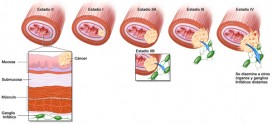

El cáncer de esófago. Tumor maligno en general y especialmente formado por células epiteliales. El esófago es el tubo hueco, muscular que transporta los alimentos y los líquidos desde la garganta al estómago. La pared del esófago comprende varias capas de tejido, incluyendo la membrana mucosa, músculo y tejido conjuntivo. El cáncer de esófago comienza en el revestimiento interior del …